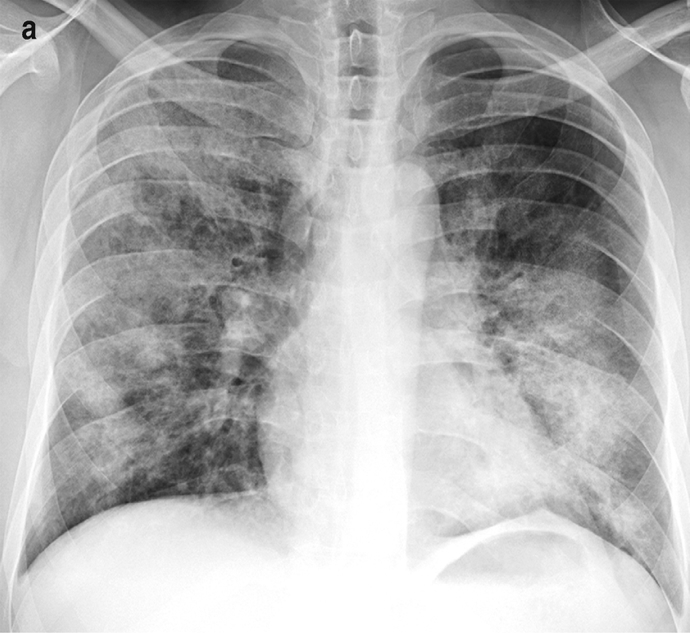

Bronchopneumonia

- Aetiology: Follows debilitating illness, surgery, or age extremes

- Strep pneumoniae, Staph aureus, H. influenzae

- Pathogenesis: Patchy, suppurative inflammation in multiple lobes

- Morphology:

- Multi-lobar and bilateral

- Patchy opacities on CXR

- Clinical Features:

- Similar to lobar pneumonia but more diffuse

- Often bilateral involvement